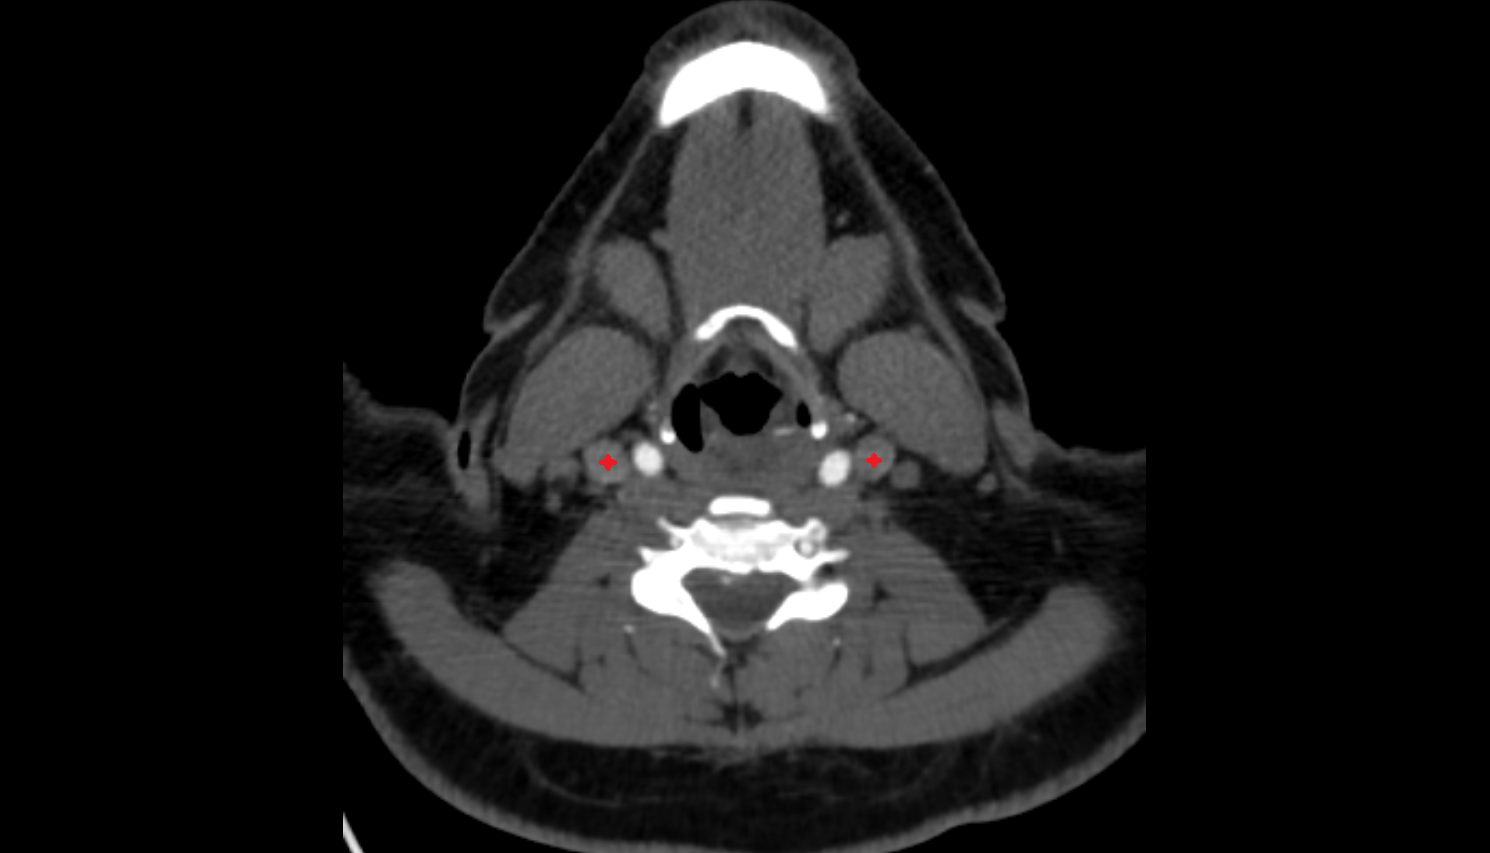

- Carotid bifurcation

- Internal carotid artery (cervical part)